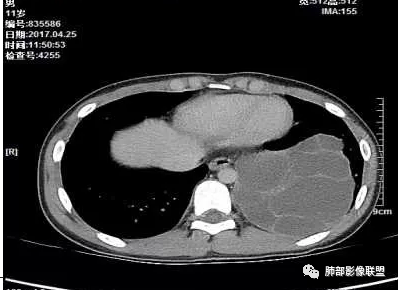

病例一

右肺上叶见一分叶状结节,增强扫描未见明显强化,考虑1.错构瘤2.支气管囊肿。

右上肺孤立性肿块性影,形态规则,边界清,密度25HU左右,没有点状钙化样密度,未见明确强化,周围可见条索,内缘肺透过度增强,有一副裂发育,考虑发育异常,支气管囊肿,CT值略高考虑合并感染;支气管闭锁,邻近未见明确支气管通行可排除;错构瘤,无强化应该是软骨型错构瘤,但是钙化太少,也可以排除;肿瘤,无强化可基本排除;结核球,不出除外

右肺实性结节,形态欠规则,边缘光滑,彭隆,分叶,近端支气管未见显示,可能堵塞,平扫密度均匀,增强扫描,可见贴边血管,实性轻度强化,肿瘤标志物无明显增高,考虑支气管囊肿,错构瘤,

中年男性,右上肺类圆形肿块影,边缘膨隆,无明显分叶毛刺,内可见点状钙化,肿块整体密度较低,增强CT值才25HU左右(说明强化不明显或根本没有强化),周围可见少许斑片索条影,考虑良性病变,首选支气管囊肿,鉴别错构瘤。

看着血管被推移,张力大,应该是无强化,良性病变,支气管闭锁一般周围肺气肿明显,倾向支气管囊肿,鉴别畸胎瘤,CCAM